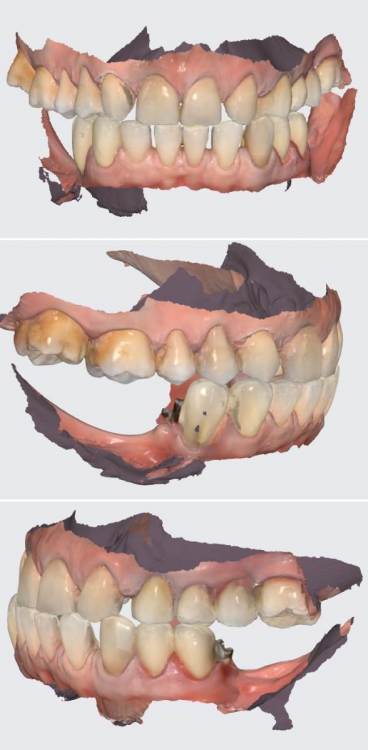

АнтонТЛТ Опубликовано 26 июня, 2023 Поделиться Опубликовано 26 июня, 2023 Техник сканировал основания и делал как цементные коронки с дыркой? Ссылка на комментарий

karasov Опубликовано 26 июня, 2023 Автор Поделиться Опубликовано 26 июня, 2023 25 минут назад, АнтонТЛТ сказал: Техник сканировал основания и делал как цементные коронки с дыркой? да Ссылка на комментарий